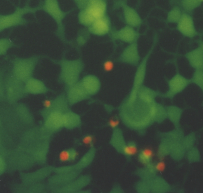

Fluorescence microscopy study

The optimum phototoxic effect of MCF7 was observed at 1.8 m g/ml ClAlPcS2 in combination with laser irradiation 25 J/cm2. Fluorescence microscopy showed (see Fig. 6) living (green fluorescence) and dead (red fluorescence) cells. Fig. 5 shows a control culture of MCF7 cells.

Fig. 5 MCF7 control cells. The cells were treated by fluorescent probes (calcein AM and ethidium homodimer) and than observed in an Olympus IX 70 fluorescent microscope, magnification 300.

a) live/dead cells b) dead cells